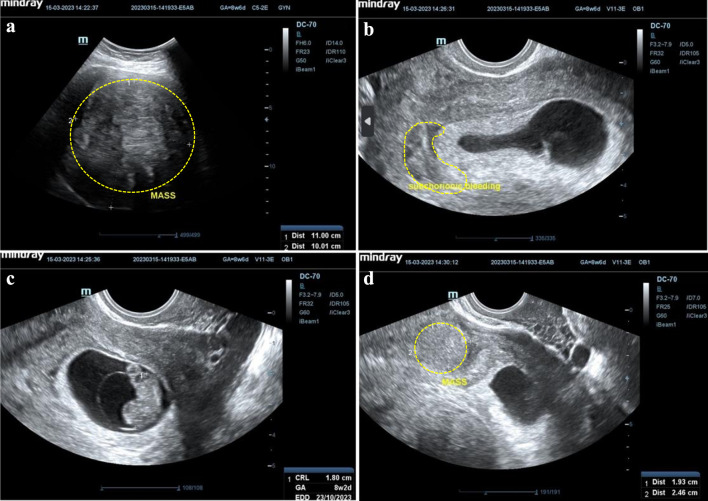

子宫肌瘤是一种良性肿瘤,影响了68.6%的女性,印度尼西亚的Hasan Sadikin医院报告的患病率在2.4%至12.46%之间。在怀孕期间,发病率降至0.1%至10.7%,但肌瘤仍可导致并发症。这个案例研究强调了一个复杂的妊娠与多个大子宫肌瘤的成功管理。孕36 ~ 37周的初迁症表现为子宫底1个大肌瘤(20 × 15 × 10 cm),前体6个小肌瘤。尽管面临这些挑战,但怀孕过程没有出现重大问题。进行了剖宫产手术,生下了一个体重2815克、身高46厘米的健康婴儿。该病例展示了对困难的产科情况的有效管理,强调了量身定制的护理和手术技巧在为母亲和婴儿实现有利结果方面的重要性。

Uterine fibroids, or myomas, are benign tumors affecting about 68.6% of women, with Indonesia's Hasan Sadikin Hospital reporting a prevalence between 2.4% and 12.46%. In pregnancy, the incidence drops to 0.1% to 10.7%, but fibroids can still lead to complications. This case study highlights the successful management of a complex pregnancy with multiple large uterine fibroids. A 36- to 37-week primigravida presented with a large intramural fibroid (20 × 15 × 10 cm) at the uterine fundus and six smaller fibroids in the anterior corpus. Despite these challenges, the pregnancy progressed without major issues. A cesarean section was performed, delivering a healthy baby weighing 2,815 g and measuring 46 cm. The case demonstrates effective management of a difficult obstetric situation, emphasizing the importance of tailored care and surgical skill in achieving favorable outcomes for both mother and baby.